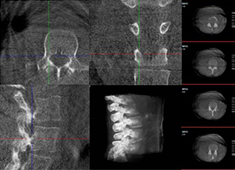

三維重建技術在醫學影像診斷中的應用價值

三維重建技術在醫學影像診斷中的應用非常廣泛,主要包括以下幾個方面:1.診斷疾病:通過三維重建技術,醫生可以更直觀、清晰地觀察到患者體內的異常情況,如腫瘤、骨折等,從而更準確地診斷疾病。...

術中三維CT如何輔助手術機器人完成手術導航

手術機器人對術中配準的要求較高,僅依靠其自身的導航定位功能還遠遠不夠,需要結合術中三維CT影像來提高導航精準度。術中三維CT是如何輔助手術機器人完成手術導航的?下面以術中三維移動C臂(PLX C7600)輔助脊柱外科手術...